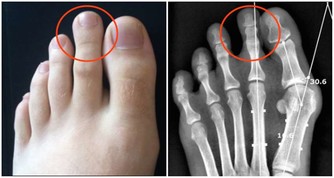

超聲科醫師檢查發現其右側陰囊空虛,右側腹股溝內可見大小約2*2*1cm的類睾丸迴聲,診斷考慮:隱睾症。

超聲科劉友員主任醫師解釋,“蛋蛋”不在陰囊裡就是俗稱的“隱睾症”。

隱睾,是指睾丸在正常發育過程中未下降或下降不全至陰囊,陰囊內沒有睾丸或只有一側有睾丸。

當發現睾丸異常時要及時來醫院進一步檢查,隱睾是可以隱藏在腹腔、腹股溝管內環等處。

目前超聲檢查是最簡便,快捷無創的檢查方法,它不僅可檢查隱睾所在的位置,還可測量隱睾大小。